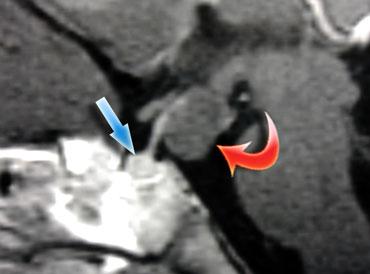

Tổn thương nằm một phần trong xoang hang phải và một phần trong hố yên có tín hiệu chủ yếu là đen trên chuỗi xung T1W này.

Nhìn chung, có ba thứ cho tín hiệu đen trên MRI: không khí, xương và dòng máu chảy nhanh. Trong trường hợp này, tín hiệu đen là do dòng máu chảy nhanh trong túi phình động mạch cảnh.

Đây là hình chụp mạch máu (angiogram) tương ứng.

Rõ ràng, đây không phải là tổn thương có thể phẫu thuật qua đường xuyên bướm (transsphenoidal)!

Các hormone vùng dưới đồi (hypothalamus) có thể kích thích (mũi tên xanh) hoặc ức chế (mũi tên đỏ) quá trình sản xuất hormone tuyến yên.

Tại sao túi phình động mạch lại gây tăng prolactin máu và tiết sữa ở bệnh nhân này?

Nguyên nhân là do chèn ép cuống tuyến yên (pituitary stalk).

Cuống tuyến yên kết nối vùng dưới đồi với tuyến yên, và các hormone được sản xuất tại vùng dưới đồi được vận chuyển đến thùy trước tuyến yên thông qua hệ thống tĩnh mạch cửa chạy dọc theo cuống.

Hầu hết các hormone này kích thích sản xuất các hormone khác tại tuyến yên (như TRH, GnRH, GHRH và CRH), nhưng dopamine được giải phóng lại ức chế sản xuất prolactin ở thùy trước tuyến yên.

Do đó, khi cuống tuyến yên bị chèn ép bởi một khối hoặc bị cắt đứt, nồng độ prolactin sẽ tăng trong khi nồng độ các hormone khác giảm.

Hiện tượng này được gọi là ‘Hiệu ứng Cắt cuống’ (Stalk Section Effect).

Đây là lý do tại sao các khối u khác ngoài u tuyến yên cũng có thể gây tăng prolactin máu.